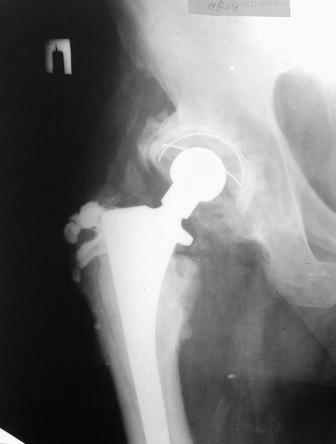

Уважаемые коллеги! Прошу Вашего совета. Больной 56л, 2.5 года назад был установлен бесцементный эндопротез.

Через 1.5 года произошло асептическое расшатывание ножи, ревизия, установлен протез с цементной фиксацией, через 1 год после этого открылся свищ. На предоставленных в архиве рентгенограммах контрастная фистулография. Распространение контраста заметно ограничено. У больного сахарный диабет II типа. Какую тактику вы бы избрали?

Постараюсь предоставить, насколько это возможно (в условиях районной больницы). Качество снимков это вопрос оцифровки, если нужно их можно переснять.Просто хотелось бы уточнить, что еще кроме ориентации компонентов эндопротеза, признаков нестабильности, степени распространения контраста там можно разглядеть?

По поводу снимков: было бы хорошо покрупнее заснять проксимальный отдел бедра и впадину, чтобы можно было оценить структуру кости и наличие

признаков нестабильности.